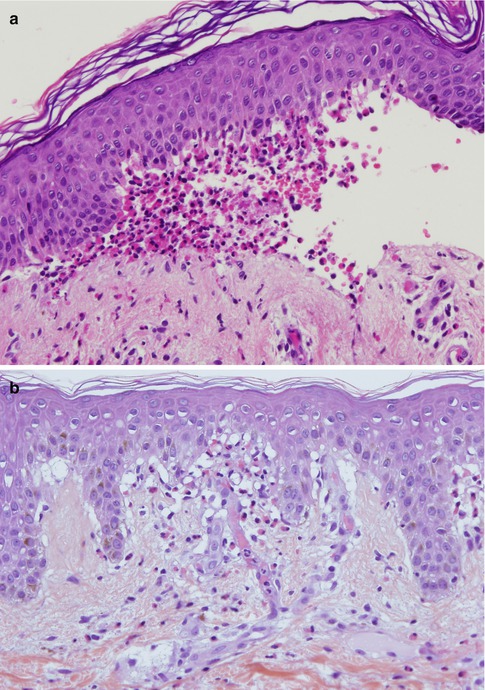

Fig. 16.5

(a) Bullous pemphigoid, DIF for IgG. Direct immunofluorescence examination of the skin of a patient reveals linear lgG deposition along the basement membrane zone (original magnification ×200). (b) Bullous pemphigoid, DIF for C3. Direct immunofluorescence examination from the same patient as in (a) shows stronger linear C3 deposition along the basement membrane zone (original magnification ×200). (c) Mucous membrane pemphigoid, DIF for IgG. Direct immunofluorescence examination of the oral mucosa of a patient reveals linear lgG deposition along the basement membrane zone (original magnification ×200). (d) Mucous membrane pemphigoid, DIF for C3. Direct immunofluorescence examination of the oral mucosa from the same patient as in (c) shows also linear C3 deposition along the basement membrane zone (original magnification ×200). (e) Dermatitis herpetiformis, DIF for IgA. Direct immunofluorescence examination of the skin shows granular lgA deposition along the basement membrane zone, with a stronger positivity at the tips of the dermal papillae (original magnification ×100). (f) Dermatitis herpetiformis, DIF for C3. Direct immunofluorescence examination of the skin shows granular C3 deposits along the basement membrane zone (original magnification ×200). (g) Linear IgA bullous dermatosis, DIF for IgA. Direct immunofluorescence examination of the skin from a patient with vancomycin-induced linear IgA bullous dermatosis shows linear lgA deposition along the basement membrane zone (original magnification ×40). (h) Epidermolysis bullosa acquisita, DIF for IgG. Direct immunofluorescence examination of the skin of a patient demonstrates intense linear lgG deposition along the basement membrane zone (original magnification ×200). (i) Epidermolysis bullosa acquisita, DIF for C3. Direct immunofluorescence examination from the same patient as in (h) shows faint linear C3 deposition along the basement membrane zone (original magnification ×200). (j) Bullous systemic lupus erythematosus, DIF for IgG. Direct immunofluorescence examination of lesional skin demonstrates intense linear lgG deposition along the dermal side of the basement membrane zone (original magnification ×400)

Bullous Pemphigoid

Biopsies from perilesional skin from patients with BP will show a typical DIF pattern with IgG and C3 deposition along the BMZ [46]. In most patients the deposits of C3 are more intense than those of IgG, and C3 deposits are found in 100 % of the patients, while IgG deposits in 70–80 % of the cases (Fig. 16.5a, b). In early stages, the deposition of immunoreactants can be exclusively of C3. In around 20 % of cases, there may be also deposits of IgM or IgA. Although this class of antibodies is not routinely studied by DIF, it has been shown that up to 40 % of patients with BP will present with linear deposits of IgE along the BMZ [47]. These IgE deposits have been related with the clinical presence of urticarial lesions in these patients and may be pathogenically related with the urticarial stage of BP.